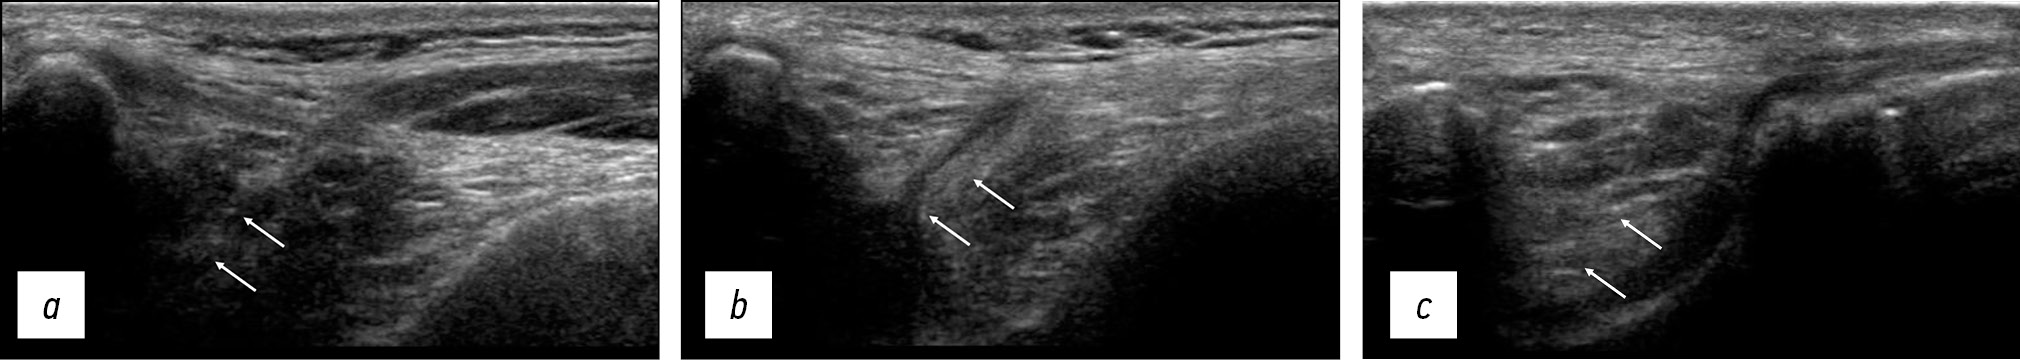

После статической ультразвуковой визуализации МПСС проводился динамический тест (рис. 6). Надколенник смещали пальцем в медиальном направлении, чтобы добиться медиального смещения примерно на 1–2 см. Затем прекращали смещение, и надколенник резко возвращался в свое нормальное положение. Давление, оказываемое на датчик для оценки боли или дискомфорта при движении надколенника, использовалось такое же, как при обычном сонографическом исследовании.

Рис. 6. Сонограммы до (а) и после (b) проведения динамического теста. Стрелками обозначена медиопателлярная синовиальная складка

Fig. 6. Sonograms before (a) and after (b) the dynamic test. Arrows indicate the mediopatellar synovial fold

При проведении динамического теста оценивались следующие критерии:

1) наличие непрерывной эхогенной складки, смещающейся по медиальному мыщелку бедренной кости во время медиального и латерального перемещения надколенника. Это подтверждало наличие МПСС, но не определяло ее патологическое состояние (рис. 6а);

2) ущемление эхогенной складки под надколенником во время медиального движения надколенника. Это позволяло выявить контакт МПСС с надколенником, так называемый внутренний импинджмент-синдром, вызванный ущемлением МПСС [20] (рис. 6б);

3) боль или дискомфорт, возникающие при динамической сонографии.